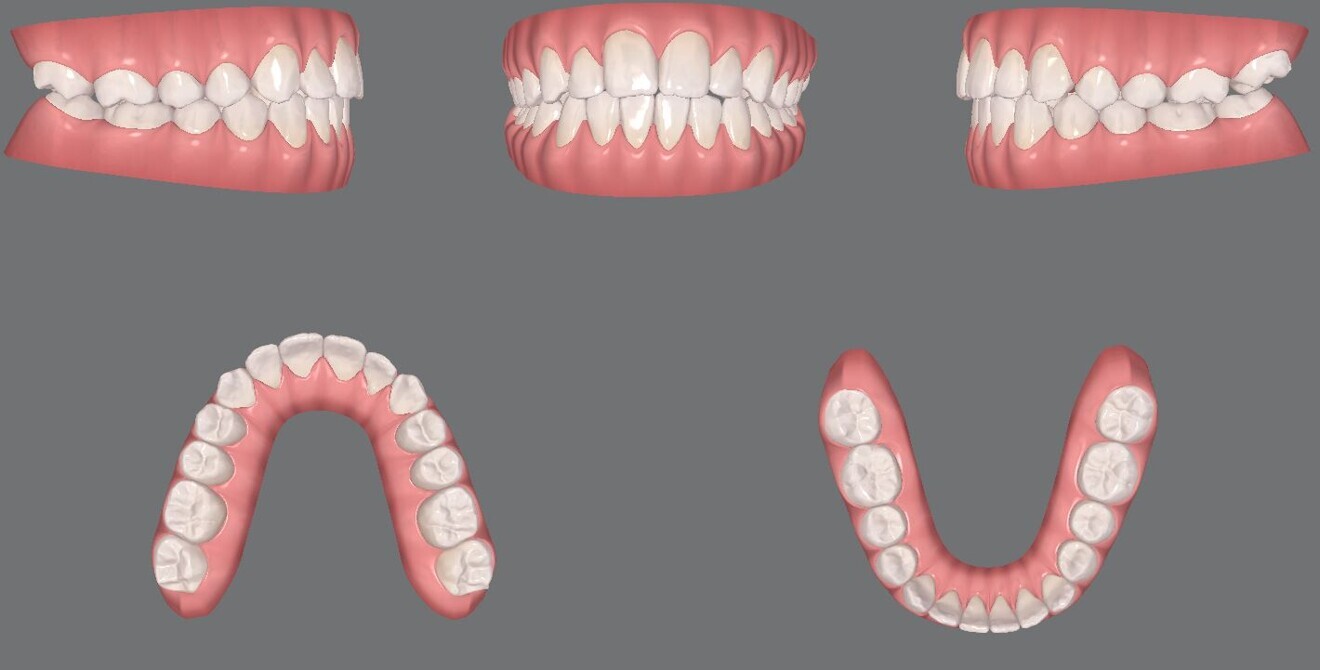

Figs. 12a–e: Pre-aligner treatment digital models

Figs. 14a–e: Mid-treatment digital models.

Figs. 24a–e: Final digital models.